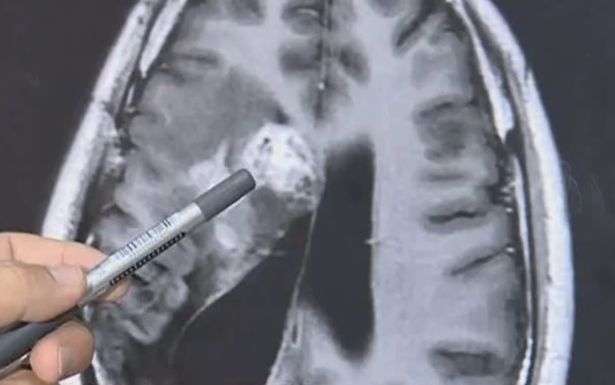

Con sán dây sống trong não bệnh nhân.

Ảnh chụp CT não của Wang.

Năm 2018, các bác sĩ phát hiện một con sán sống trong não bệnh nhân. Ở thời điểm đó, các bác sĩ chỉ định biện pháp chữa trị không phẫu thuật vì ký sinh trùng nằm ở khu vực nhạy cảm, rất khó phẫu thuật.

Đến nay, sán dây vẫn sống trong não Wang nên các bác sĩ ở bệnh viện tỉnh Quảng Đông phải phẫu thuật mở hộp sọ. Ca phẫu thuật kéo dài 2 giờ kết thúc tốt đẹp khi các bác sĩ gắp được con sán dây, chủ yếu ký sinh ở chó mèo, ra ngoài.